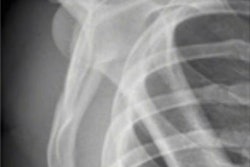

In the U.S., there is a lot of focus on the "overhead throwing athlete" and associated injuries of shoulder and elbow. This is different from Norway. We do not play baseball, football is by far the largest sport, and we see a lot of injuries of the hip, knee, and ankle. Other sports are popular, including ice hockey, basketball, martial arts, and bicycling. Norway is known for skiing, but this surprisingly does not generate too many injuries that need imaging. A very active population leads to imaging not only of athletes in their twenties. Children and old people are active and becoming injured. Thus, the field expands, as MSK imaging of children is challenging because of a lot of developmental variations, and MSK imaging of old people is challenging because of coexistent degenerative changes. The injuries themselves may not change in presentation from year to year, but there is a change in imaging strategy that has evolved throughout the last 20 years: The availability of MRI scanners in Norway has steadily increased. The demand from clinicians and especially patients for early MRI scanning is increasing. These developments change the work of a radiologist. We see changes that we didn't see previously because we are imaging earlier than before. We make findings that the orthopedic surgeons did not know a few decades ago, and the pressure on therapy may increase because of our findings. On the other hand, early imaging may also be important as a therapy strategy; if we can clarify that nothing vital is injured, the clinician may guide the patient into the correct therapy regime.

Imaging can detect both subtle and obvious injuries associated with sporting activity. Early stress reactions in bone, tendons, and soft tissues can be seen, as well as all sorts of ruptures and fractures. However, some injuries are subtle, and if you don't look for them, you will not find them. A sports radiologist must look for smaller changes than other radiologists are used to. This may be because the athlete is imaged very early after an injury or after the start of a complaint, and smaller injuries may be more important in an athlete than in other patients.

Most sports injuries are evaluated with ultrasound, ordinary x-rays, and MRI. CT is seldom required. The radiation dose from an x-ray is negligible but should nevertheless be considered when deciding which modality should be used for a particular injury. Sometimes x-ray images are the problem-solver; therefore, they should not be forgotten! MSK ultrasound is not yet widely used in Norway but there is good access to MRI. MRI is harmless but generates a lot of images and a lot of details. Overexposure to radiation is probably not a problem in sports imaging, but overexposure to imaging for radiologists can be a problem. Sometimes one will find something new for every study made on a particular patient, and it can be hard to sort out the truly relevant findings.